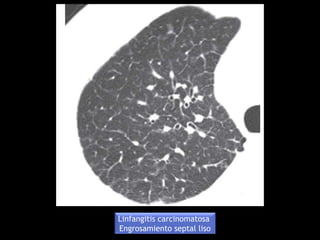

Linfangitis carcinomatosa

Engrosamiento septal liso